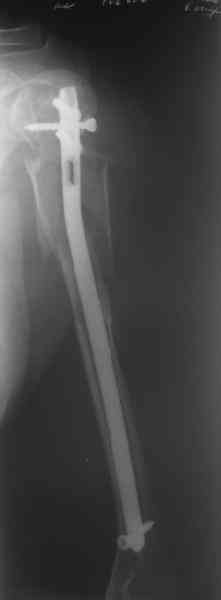

Добрый вечер!

Приложение как пример.

Что иллюстрирует этот пример? Это была множественная травма? Если это был изолированный перелом, то "золотой стандарт" - консервативное лечение.

Консервативно он уже лечился до этой операции в течение трёх с половиной месяцев.

А именно такой вариант операции выбран из экономических соображений.

вообще, торчашие в субакромиальное пространство шипы оставляют неизгладимое впечатление. Не думаю, что таким имплантом есть смысл гордиться

Снимок с имплантом из металла с памятью формы получился "sexy", но нарушены все каноны остеосинтеза. Потому что при комбинации двух ущербных систем одновременно повреждается внутри канальное и наружное кровообращение.

Кроме интрамедуллярного остеосинтеза, имеются другие варианты фиксации, наружный фиксатор и например здесь перелом плеча с повреждением нерва леченный открытым методом. Применен задний доступ с инспекцией нерва, межфрагментарная компрессия, фиксация узкой пластиной 4.5 мм.